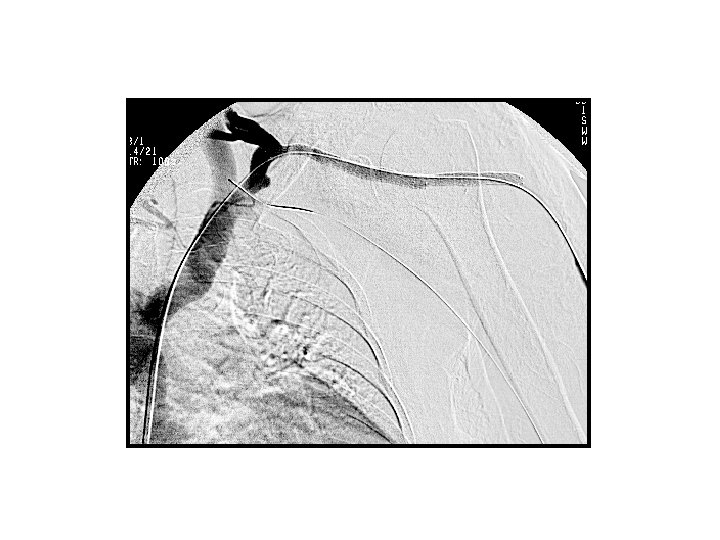

fibrin kılıf • Kateter girim yerinden ucuna kadar çepeçevre kateteri saran inflamatuar hücre, kollajen ve düz kas hücrelerinden oluşan proteinöz kılıf • İlk 24 saatte oluşmaya başlayabilir • Tek yönlü valv gibi davranır. Sıvı vermede problem yoktur. Esas sorun kateterden kan çekememektir.

fibrin kılıf • Tedavi seçenekleri – Fibrinolitik ajan (infüzyon / lock tdv) – Mekanik olarak fibrini temizlemek • Kılıf sıyırma (snare) • Balon dilatasyonu – Farklı bir akses oluşturma